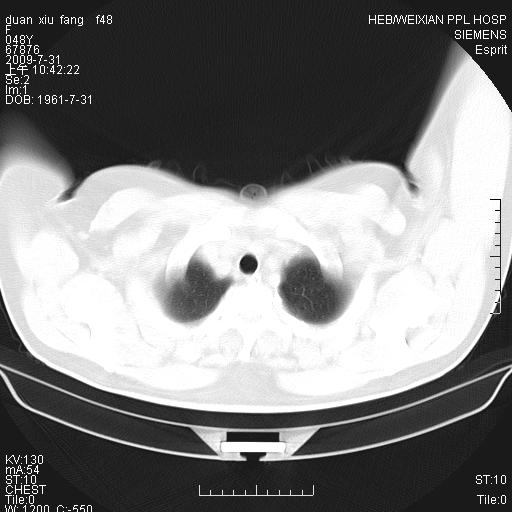

标题: CT22224:肺部肿块

f,48,主因咳嗽咳血来我院检查,无发热。

谈一谈个人的看法:机器性能应该不错,可惜扫描方法不太正确,即没有及时薄层扫描图像,也没有增强检查,这样的检查方法不正确的图片拿来研究只能是猜一猜:右肺下叶阻塞性改变,建议进一步检查删除肺癌。

支气管镜检查未见异性细胞,抗炎治疗20天,肿块明显缩小。